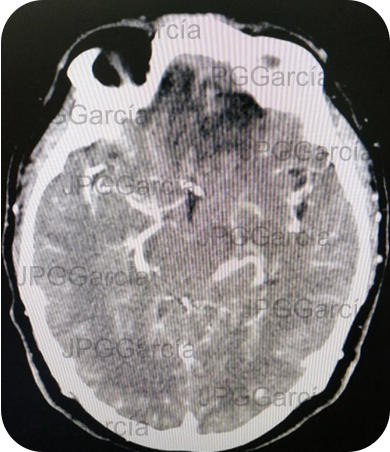

Tomografía contrastada que muestra resección de la lesión tumoral y área cicatricial post quirúrgica